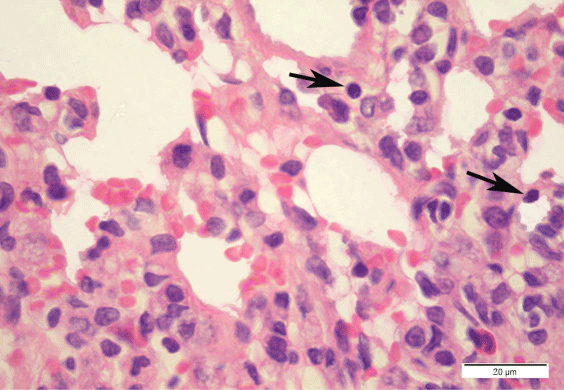

Figure 17: A photomicrograph of a DEHP recovery rat alveolar tissue showing extravasated blood cells in alveolar lumens, with less inflammatory cell infiltration. Some necrotic type II pneumocytes with pyknotic nuclei are shown (black arrow). (H & E x1000).